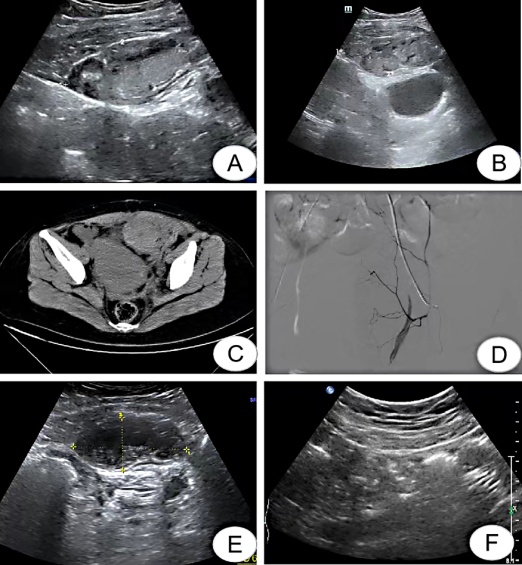

1 资料与方法病例1患者31岁,因“停经37周,发现血压升高3 d”于2022年3月24日入院。既往体健,生育史:0-0-1-0。入院第2天因“重度子痫前期”行子宫下段剖宫产术。手术过程顺利,术后予解痉、降压、补充白蛋白、预防感染以及补液支持等治疗,术后血压波动于148~162/98~108 mmHg(1 mmHg=0.133 kPa)。剖宫产术后24 h,予低分子肝素针1支皮下注射1次/d预防发生血栓。术后第2天下午患者出现胸闷,血氧饱和度(SpO2)95%,肺动脉CTA提示肺栓塞,低分子肝素针改为2次/d皮下注射抗凝及吸氧等支持治疗。术后第6天患者如厕后突发左下腹持续性疼痛,程度剧烈。查体:生命征平稳,左下腹直肌走行区域触痛明显。急诊超声提示:左盆腔与前腹壁之间可见一不均回声团块,大小约7.26 cm×3.88 cm×5.56 cm(图 1A)。急查血红蛋白126 g/L,血液炎症指标正常。考虑腹直肌鞘血肿可能,鉴于患者生命体征平稳,即停用低分子肝素针,予腹带捆绑局部加压包扎治疗,密切监测血肿及生命体征情况。随后监测中患者超声及腹部CT提示血肿较前增大(图 1B、1C),行介入治疗止血。术中造影显示左侧腹壁下动脉分支可见造影剂外溢(图 1D),行动脉栓塞术,术后患者腹痛不适消失,于栓塞术后第3天出院。1个月后随访,超声提示血肿减小,约6.25 cm×2.88 cm×3.10 cm大小(图 1E);6个月后随访,超声提示血肿已完全吸收(图 1F)。

| A:3月31日17:28超声提示血肿大小;B:3月31日19:30超声提示血肿较前增大;C:3月31日22:33血肿计算机断层扫描;D:介入术中造影剂外溢;E:5月10日超声提示血肿较前减小;F:9月20日超声提示血肿消失 图 1 病例1影像检查结果 |